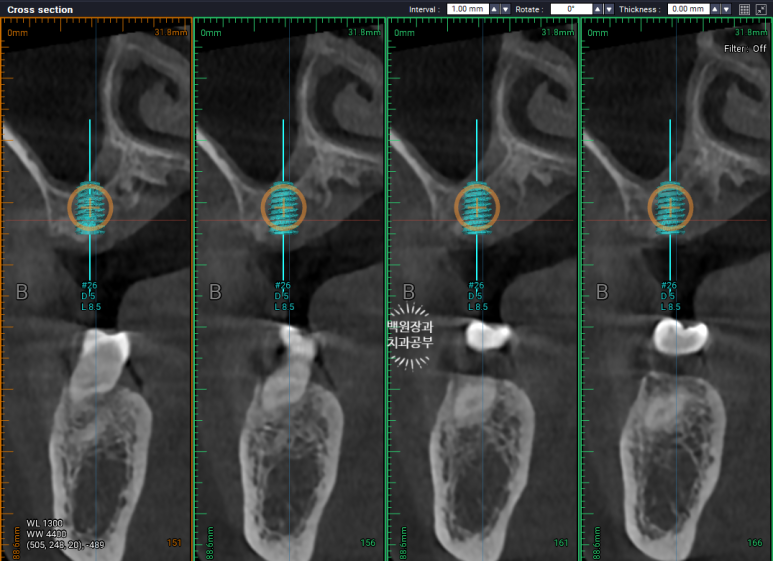

약 4개월이 지난 시점에서,

이식해두었던 뼈이식 재료와, 함께 재생된 새로운 잇몸뼈가 양질의 구성을 이루고 있음을 눈으로 직접 확인 후,

해당 부위에 임플란트를 새로 심어드렸어요.

오스템 TS BA 직경 5.0mm 길이 8.5mm 임플란트를 심어드렸는데,

딱 보시더라도 기존의 임플란트보다 훨씬 두꺼운 것을 보실 수 있을거에요.

큰어금니 부위는 임플란트가 하중을 많이 받기 때문에,

가능한한 두꺼운 임플란트를 심어드리는게 아~주 중요합니다.

얇은 임플란트를 심으면 부러질 가능성이 아주 높아지기 때문이에요.